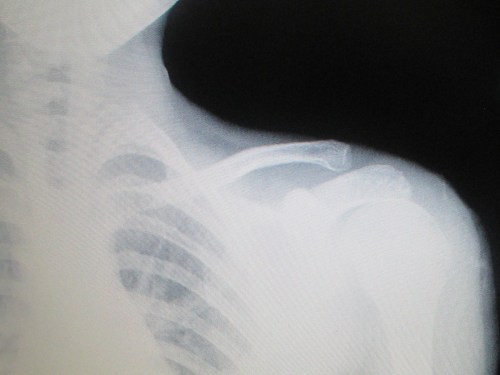

Remember my recent blog about how my 10-year-old son, Aden, hurt his shoulder and I neglected to seek medical attention for 3 days because I didn’t think he was really injured? And then it turned out to be a fractured collarbone, torn ligaments and a medium sprain? (Oops.)